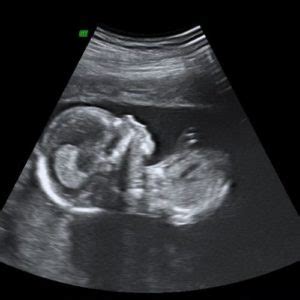

11. Schwangerschaftswoche: Erkennbare Körperteile

Bei einem Ultraschallbild aus der 11. Schwangerschaftswoche lassen sich die Körperteile des Babys bereits erkennen. Im Verhältnis zum Rest des Körpers ist der Kopf des Fötus größer. Auf dem Ultraschallbild sind oft die Beine des Fötus zu sehen, die an den Knien im rechten Winkel gebeugt sind.

12. Schwangerschaftswoche: Ein kleiner Mensch

Ihr Baby ist in der 12. Schwangerschaftswoche ein vollständiger kleiner Mensch, obwohl es nur rund fünf Zentimeter misst. Mit etwas Glück ist auf dem Ultraschallbild jetzt schon zu sehen, wie Ihr Baby gähnt. Der Kopf ist im Vergleich zum restlichen Körper noch überdimensional groß.